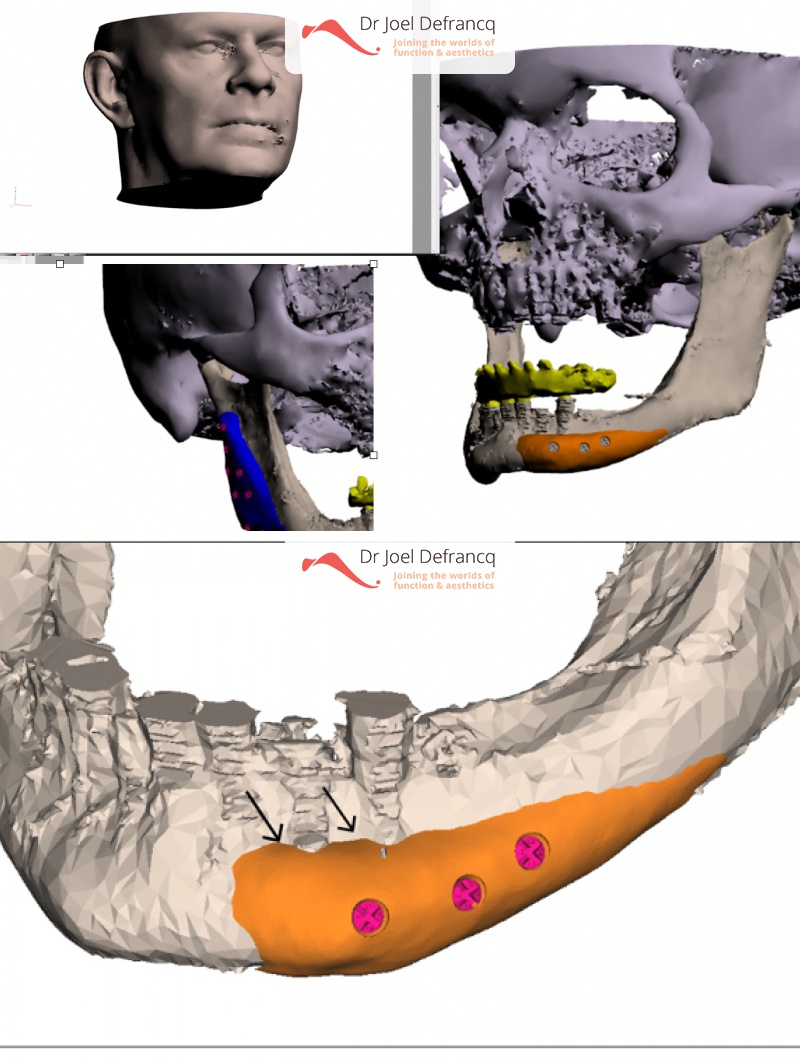

Kaakchirurgie

- Verlenging bovenkaak (Le Fort I)

- Uitgebreide been greffe van de posterieure heup

- Kaakhoek augmentatie